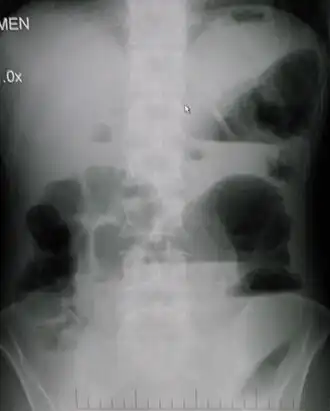

![]() Radiografía de abdomen que demuestra obstrucción intestinal reflejada por la ausencia de gases en la ampolla rectal. | ||

Radiografía simple de abdomen:

- En bipedestación o decúbito lateral.

- Múltiples niveles hidroaéreos a diferentes niveles, asas de intestino delgado dilatadas en la parte proximal a la obstrucción y la ausencia o disminución de aire en la zona distal.

- En fases tardías, si existe estrangulación, el edema de la mucosa y submucosa, asociados a la necrosis determinan la aparición de imágenes con aspecto de impresiones dactilares.

- Perforación intestinal: presencia de aire subdiafragmático en bipedestación o aire libre en la cavidad peritoneal en decúbito lateral izquierdo.

- Íleo paralítico es característico que la dilatación de las asas afecte o pueda afectar a todo el intestino. Sin embargo, la presencia de niveles hidroaéreos hace difícil su diferenciación de la oclusión intestinal.